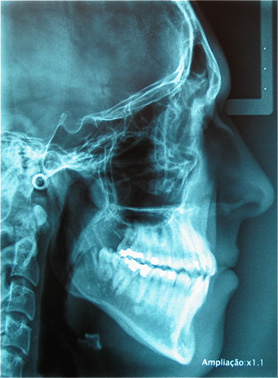

Numa primeira consulta, são recolhidas informações junto do paciente que, juntamente com fotografias, modelos de estudo e radiografias (ortopantomografia e telerradiografia), serão rigorosamente analisados, de forma a proporcionarem uma boa base para a elaboração de um plano de tratamento ortodôntico e colocação do aparelho dentário para o seu caso (poderão ser necessários outros exames clínicos adicionais).

Ortodontia é a especialidade da Medicina Dentária que corrige a posição e alinhamento dos dentes e corrige a posição dos dois maxilares, dando a posição correta aos maxilares, melhorando a saúde das articulações temporomandibulares não esquecendo a face e o perfil estético do paciente.

É da associação da cefalometria com os restantes estudos já mencionados que nasce um diagnóstico e plano de tratamento ortodôntico.

Na Ortodontia, os exames e os estudos são indispensáveis para um correto diagnóstico, para a elaboração de um plano de tratamento adequado e colocação do aparelho dentário no paciente.

Apinhamento dentário com os dentes caninos em desoclusão (classe II, divisão 2).

![]() |

Após dois anos de tratamento ortodôntico.